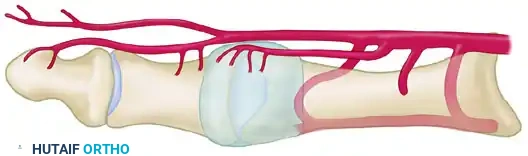

The vascular supply to the first metatarsal head is delicate and highly susceptible to iatrogenic injury during corrective osteotomies and capsular releases. A thorough comprehension of the extraosseous and intraosseous arterial networks is mandatory for any reconstructive foot and ankle surgeon.

The Medial and Plantar Blood Supply

The primary blood supply to the first metatarsal head is derived from the first dorsal metatarsal artery, the first plantar metatarsal artery, and the superficial branch of the medial plantar artery. These vessels give rise to a rich network of pericapsular perforators that enter the metatarsal head distally. The principal nutrient artery enters the lateral aspect of the metatarsal shaft proximally.

Surgical Warning: The site of a cortical osteotomy must remain strictly within the interval between the pericapsular perforators distally and the nutrient artery proximally. Violation of this safe zone significantly increases the risk of osteonecrosis.

The Dorsal Vulnerability

From a dorsal perspective, the relationship between the osteotomy site, the nutrient artery, and the distal pericapsular perforators becomes highly apparent. The first dorsal metatarsal artery and its branching network are especially vulnerable to overpenetration of the lateral cortex by an oscillating saw during the osteotomy cut.